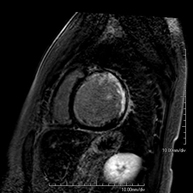

Exploració per estudiar la musculatura i dels tendons que s'originen en aquest nivell, com els tendons isquiotibials, lesió sovint en esportistes. La durada aproximada és de 16 minuts. No empra radiació ionitzant. - RM de Cuixa

Exploració ideal per estudiar les lesions en músculs isquiotibials i quàdriceps, sovint lesionats en esportistes. També permet una bona valoració de tendons i de nervis perifèrics. La durada aproximada és de 20 minuts. No utilitza radiació ionitzan. - RM de Genoll